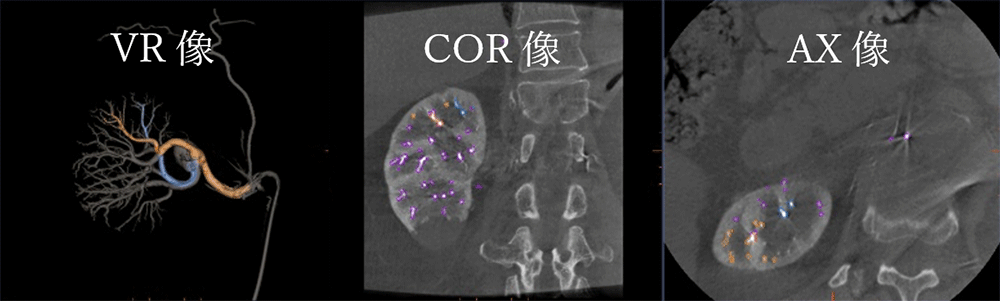

IGS630_Tokaidaigaku_06.png図6.還流領域の確認

“Virtual Injection”は,造影シミュレーションを行うアプリケーションであるが,血管の還流領域を観察する事も可能である.部分的脾動脈塞栓術(PSE)などに有効に使用することが可能である.どの血管を塞栓したらどの程度脾臓の体積を縮小させることが出来るのか視覚的に確認しやすくなる.PSEの画像がなかったので腎臓に対して”Virtual Injection”を使用してプランニングした画像を参考として提示する(図6).